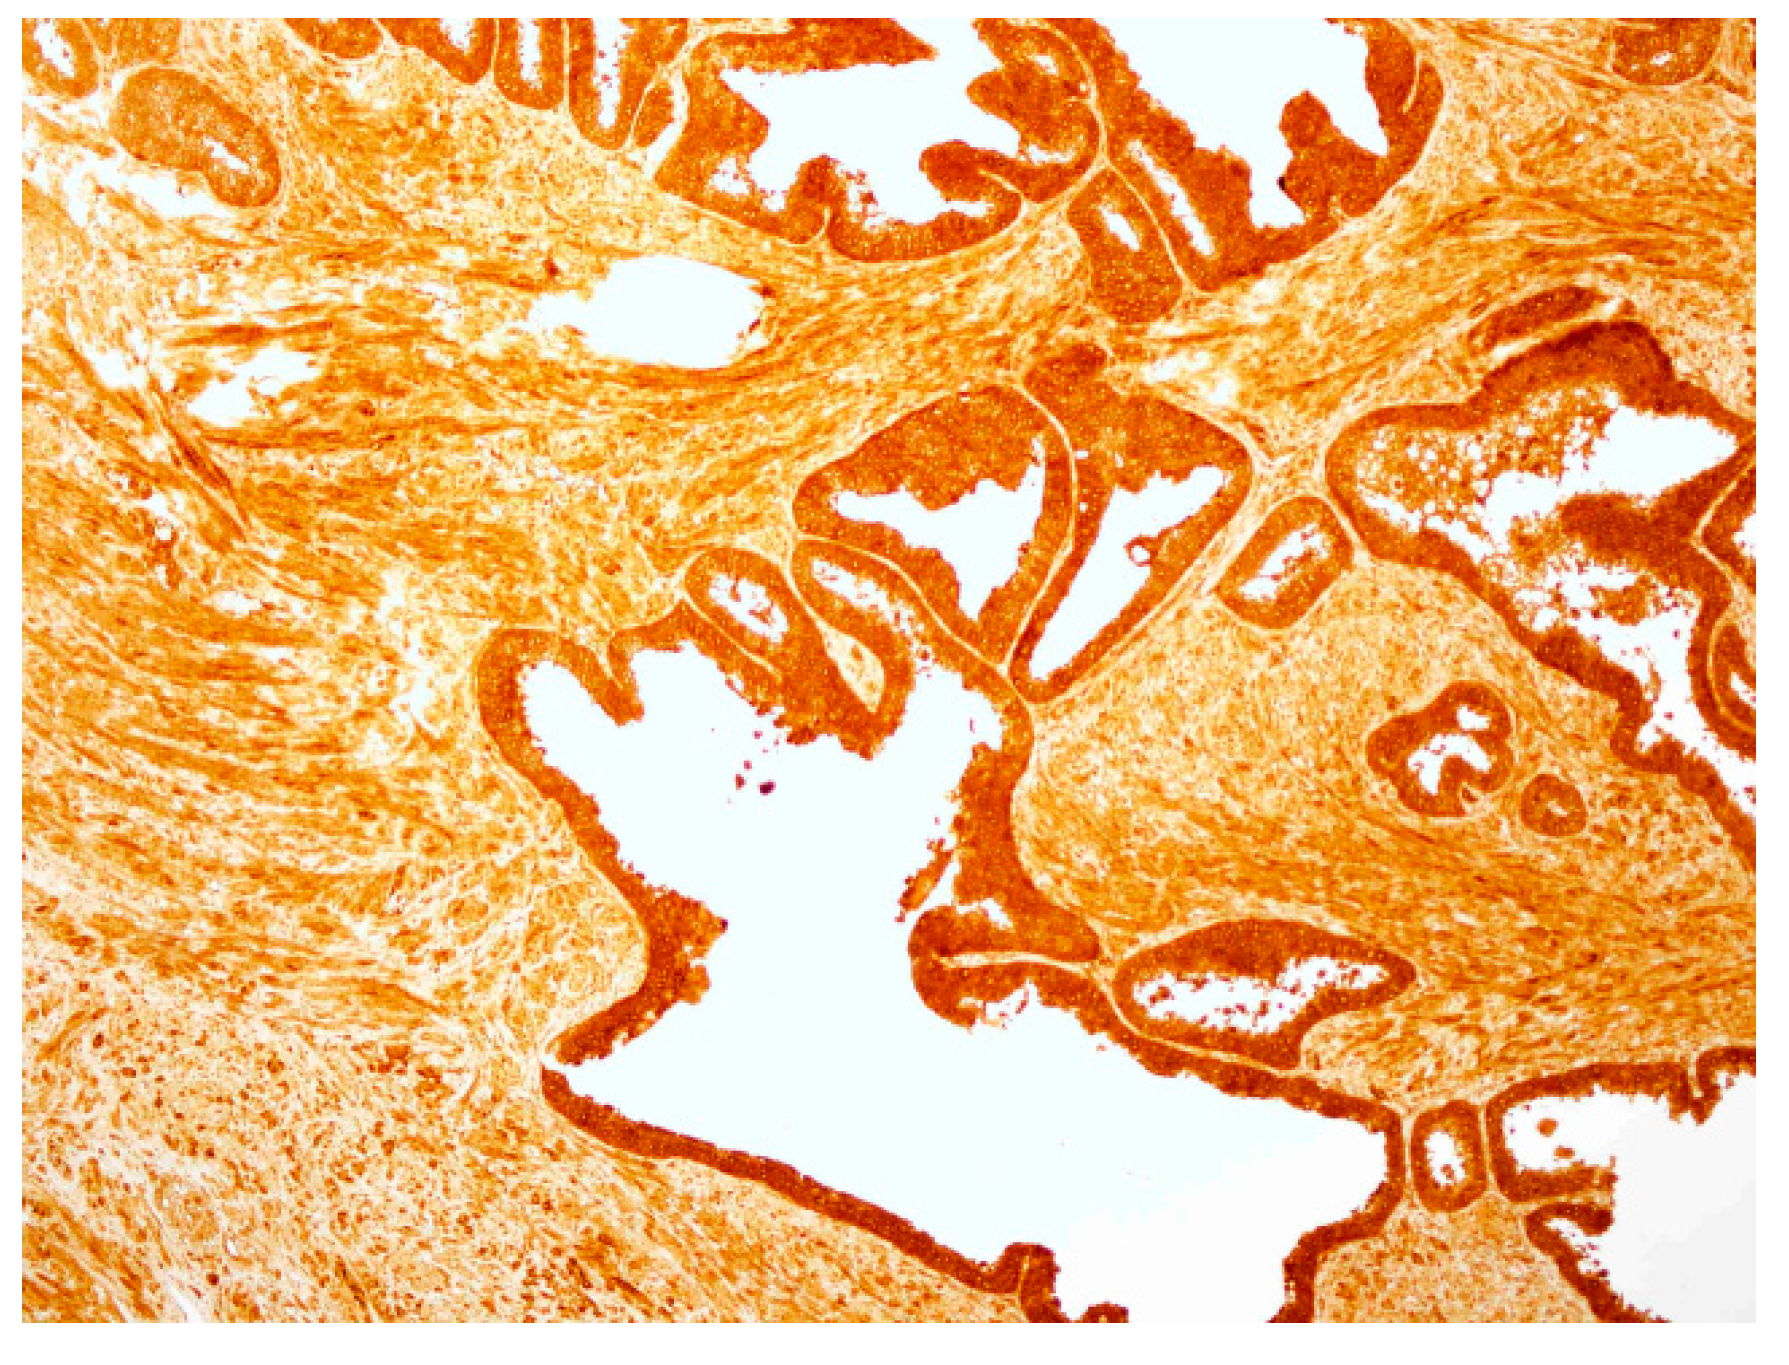

2.4. hPSA Immunohistochemistry with Biotynilated Antisense Peptide and Monoclonal Antibody

3.6. Immunohistochemical Staining of hPSA: Protocol 1 and Protocol 2

3.6.1. Protocol 1 (Standard IHC Staining Technique)

- The specimen was covered with peroxidase block, i.e., 100 μL of 0.03% hydrogen peroxide containing sodium azide (Dako, Glostrup, Denmark), and incubated for four minutes. Following this procedure, the specimen was gently rinsed with phosphate buffered saline (PBS), and placed in a fresh buffer bath.

- Primary monoclonal mouse anti-human PSA antibody (Clone ER-PR8, Code M0750; Dako, Glostrup, Denmark) was diluted with standard diluent containing 0.05 mol/L TRIS-HCl buffer and a 1% bovine serum albumin (BSA). 100 μL of primary antibody diluted in the proportion 1:100 was used to cover the specimen. After 30 min of incubation at room temperature, the specimen was gently rinsed with PBS and placed in a fresh buffer bath.

- 100 μL of HRP-labelled polymer conjugated to goat anti-mouse immunoglobulins in Tris-HCl buffer containing stabilizing protein and an anti-microbial agent (Dako, Glostrup, Denmark) was applied to cover the specimen, followed by a 30 min incubation. After 30 min of incubation, the specimen was gently rinsed with PBS and placed in a fresh buffer bath.

- The specimen was covered with 100 μL of AEC + substrate-chromogen solution for 10 min, i.e., 3-amino-9-ethylcarbazole containing hydrogen peroxide, stabilizers, enhancers and anti-microbial agent (Dako, Glostrup, Denmark). After that period the specimen was again rinsed with PBS.

- The slides were immersed in a bath of aqueous hematoxylin (Mayerr’s hematoxylin), and rinsed gently in a distilled water bath. Slides were dipped 10 times into a bath of ammonia (0.037 mol/L), and rinsed in a bath of distilled water for four minutes.

- The specimens were mounted and coverslipped with the non-aqueous permanent mounting medium Ultramount.

- Biotinylated antisense peptide AVRDKVG (GenScript, Piscataway, NJ, USA) directed to PSA epitope 53–59 (RHSLFHP) was used to cover the specimen. Five milligrams of Biotin-AVRDKVG antisense was diluted in 2.5 mL PBS. Dilutions 1:10, 1:50, 1:100, 1:200 and 1:500 were applied to cover the specimen. A 100 μL volume was used per section. After 30 min of incubation, each specimen was gently rinsed with PBS and placed in a fresh buffer bath.

- Anti-biotin antibody conjugated to HRP (ab34645, Abcam, Cambridge, UK) was applied to cover the specimen. Of the antibody 10 mg/2 mL was diluted 1:100. One hundred microliters of the diluted antibody was applied to cover each specimen, followed by a 30 min incubation. After the incubation, the specimen was gently rinsed with PBS and placed in a fresh buffer bath.

- The specimen was covered with 100 μL of AEC + substrate-chromogen solution for 10 min, i.e., 3-amino-9-ethylcarbazole containing hydrogen peroxide, stabilizers, enhancers and an anti-microbial agent (Dako, Glostrup, Denmark). After that period the specimen was again rinsed with PBS.

- The slides were immersed in a bath of aqueous hematoxylin (Mayerr’s hematoxylin), and rinsed gently in a distilled water bath. The slides were dipped 10 times into a bath of ammonia (0.037 mol/L), and then rinsed in a bath of distilled water for four minutes.

- The specimens were mounted and coverslipped with non-aqueous permanent mounting medium Ultramount.

| Patient No.\Dilutions * | 1:10 | 1:50 | 1:100 | 1:200 | 1:500 |

|---|---|---|---|---|---|

| 1 | 0 | 1 | 2 | 0 | 0 |

| 2 | 0 | 1 | 2 | 1 | 0 |

| 3 | 0 | 2 | 3 | 1 | 0 |

| 4 | 0 | 1 | 2 | 1 | 0 |

| 5 | 0 | 1 | 3 | 1 | 0 |

| 6 | 0 | 1 | 2 | 1 | 0 |

| 7 | 0 | 1 | 2 | 1 | 0 |

| Sum of scores | 0 | 8 | 16 | 6 | 0 |